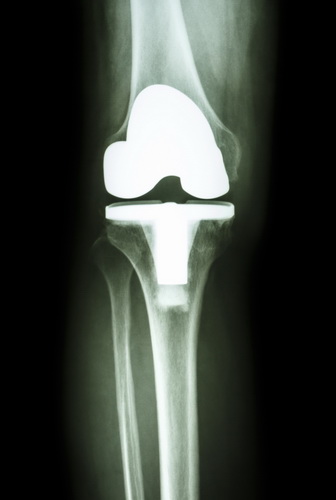

- Тотальное эндопротезирование. Методика, применяемая при необходимости замены обеих частей сустава. Операция позволяет полностью восстановить его функции, а благодаря профессионализму зарубежных ортопедов сопряжена с минимальными рисками. К примеру, эндопротезирование коленного сустава за рубежом,проводимое с использованием анатомических имплантов, обеспечивает способность полноценно сгибать ногу, ходить и даже заниматься спортом. При тотальной замене удаляются абсолютно все пораженные ткани, после чего на их место фиксируются искусственные протезы. С целью более точного их позиционирования врачи за границей используют прогрессивные системы компьютерной навигации. С их помощью также удается повысить результативность операции: за счет правильной установки импланта срок его службы значительно увеличивается.

В зарубежных клиниках осуществляется успешная замена суставов различной локализации: коленного, тазобедренного, голеностопного, плечевого, локтевого. Операции выполняются под местной или общей анестезией и в среднем длятся от 1 до 3 часов (все зависит от объема вмешательства и используемых методик). Благодаря тому, что за границей врачи располагают ультрасовременным медицинским оборудованием, прилегающие ткани практически не подвергаются повреждению. Все манипуляции выполняются через небольшие разрезы, а искусственные импланты надежно фиксируются при помощи инновационных цементных, бесцементных или гибридных технологий.